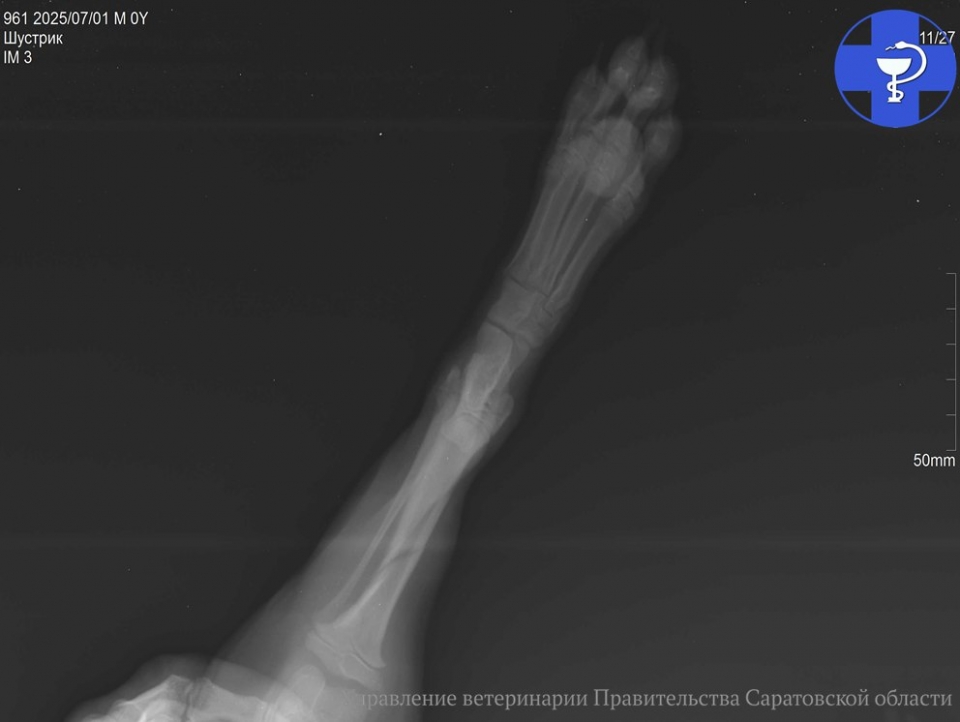

После осмотра ветеринары сделали щенку рентген. Диагноз — косой оскольчатый перелом большеберцовой кости, одной из основных в голени. Для активных щенков такие травмы, к сожалению, не редкость, отмечают ветеринары.

Шустрику была назначена консультация у ветврача-травматолога для проведения остеосинтеза — операции по восстановлению кости.